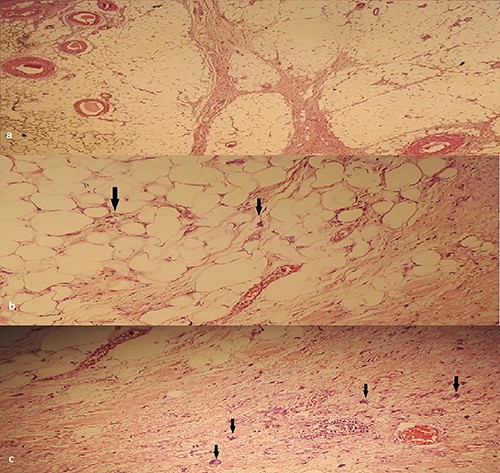

An anatomopathological examination of the surgical specimens coupled, in four out of six cases, with an immunohistochemical study using the anti-MDM2 antibody concluded to a well-differentiated LSC in four cases and a dedifferentiated LSC in the two other cases (Fig. 3).

(a) HEX4: Lobules of adipocyte cells separated by fibrous septa. (b) HEX400: large nuclei, (c) HEX400: atypical cells: enlarged nuclei with irregular contours.